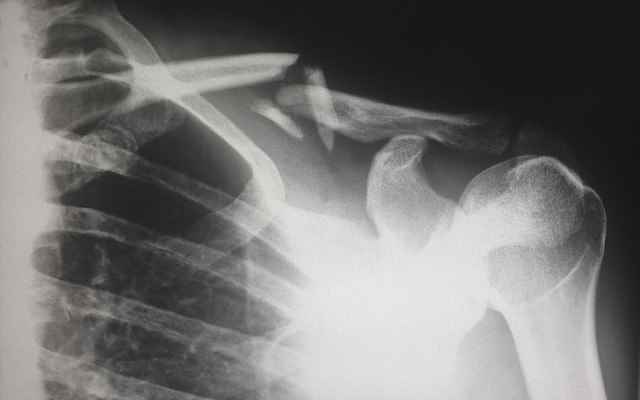

6. 외상이나 골절

골다공증의 특징적인 증상 중 하나는 외상이나 힘이 거의 없는 상태에서 골절의 위험이 증가한다는 것입니다. 허리를 굽히거나 기침을 하거나 심지어 가벼운 돌기가 있는 경우에도 골절이 발생할 수 있는데, 특히 엉덩이, 척추, 손목과 같은 체중이 많이 나가는 뼈에 골절이 발생할 수 있습니다. 큰 부상 없이 골절을 경험했다면, 향후 골절과 합병증을 예방하기 위해 의사와 함께 뼈 건강에 대한 근본적인 관심사를 조사하는 것이 필수적입니다.